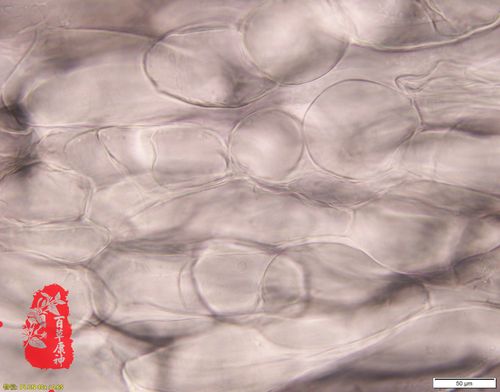

北沙参显微鉴别图

北沙参显微鉴别图,北沙参和沙参的区别

北沙参显微鉴别